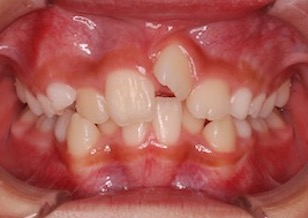

9歳女子の患者さんで叢生(ガタガタの歯並び)を主訴に来院されました。

上下顎歯列に叢生(ガタガタの歯並び)を認めます。

Before Ⅰ、Ⅱの写真は、初診時の口腔内写真です。